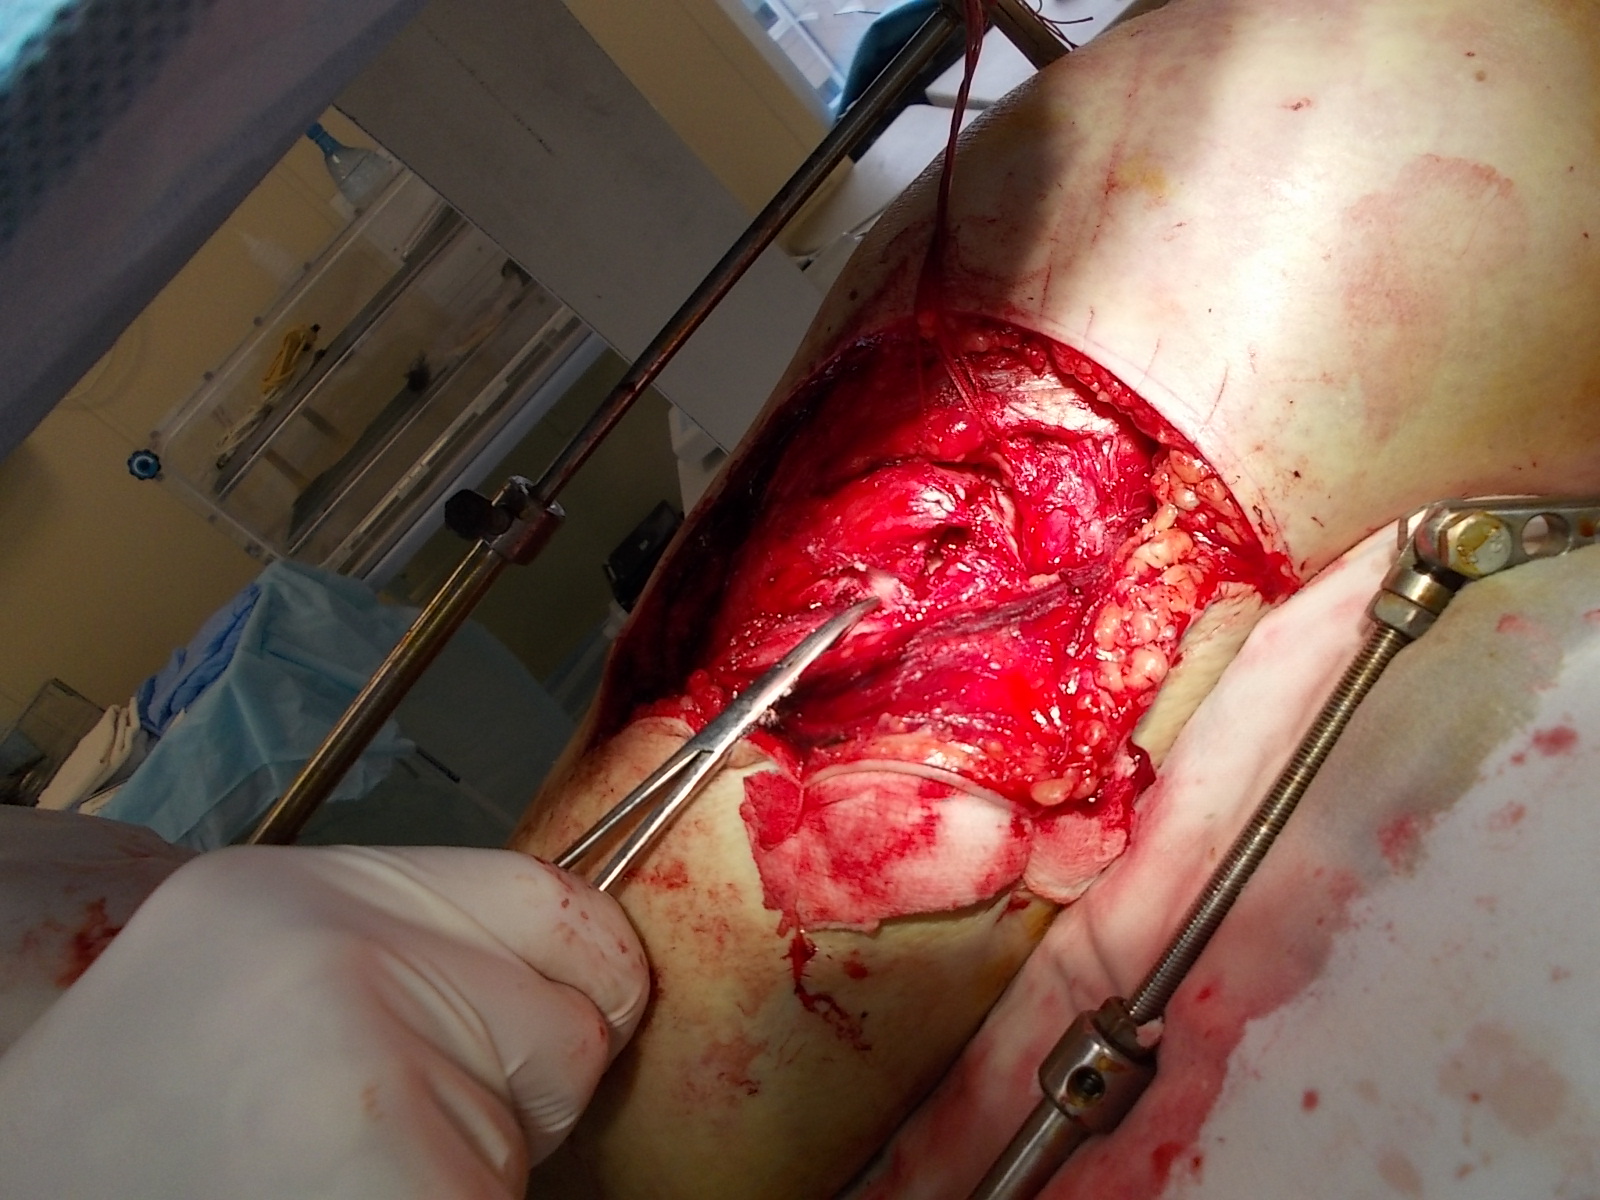

Использование материала Остеоматрикс при импрессионном оскольчатом переломе наружного мыщелка большеберцовой кости по типу Schatzker II.

Операция - открытая репозиция, остеосинтез большеберцовой кости опорной пластиной с костной ксенопластикой маетриалом "Остеоматрикс". На контрольных снимках в три и шесть месяцев имеется консолидация перелома, миграции фиксатора нет, имеется остеоинтеграция ксенопластического материала. Функция коленного сустава полная.